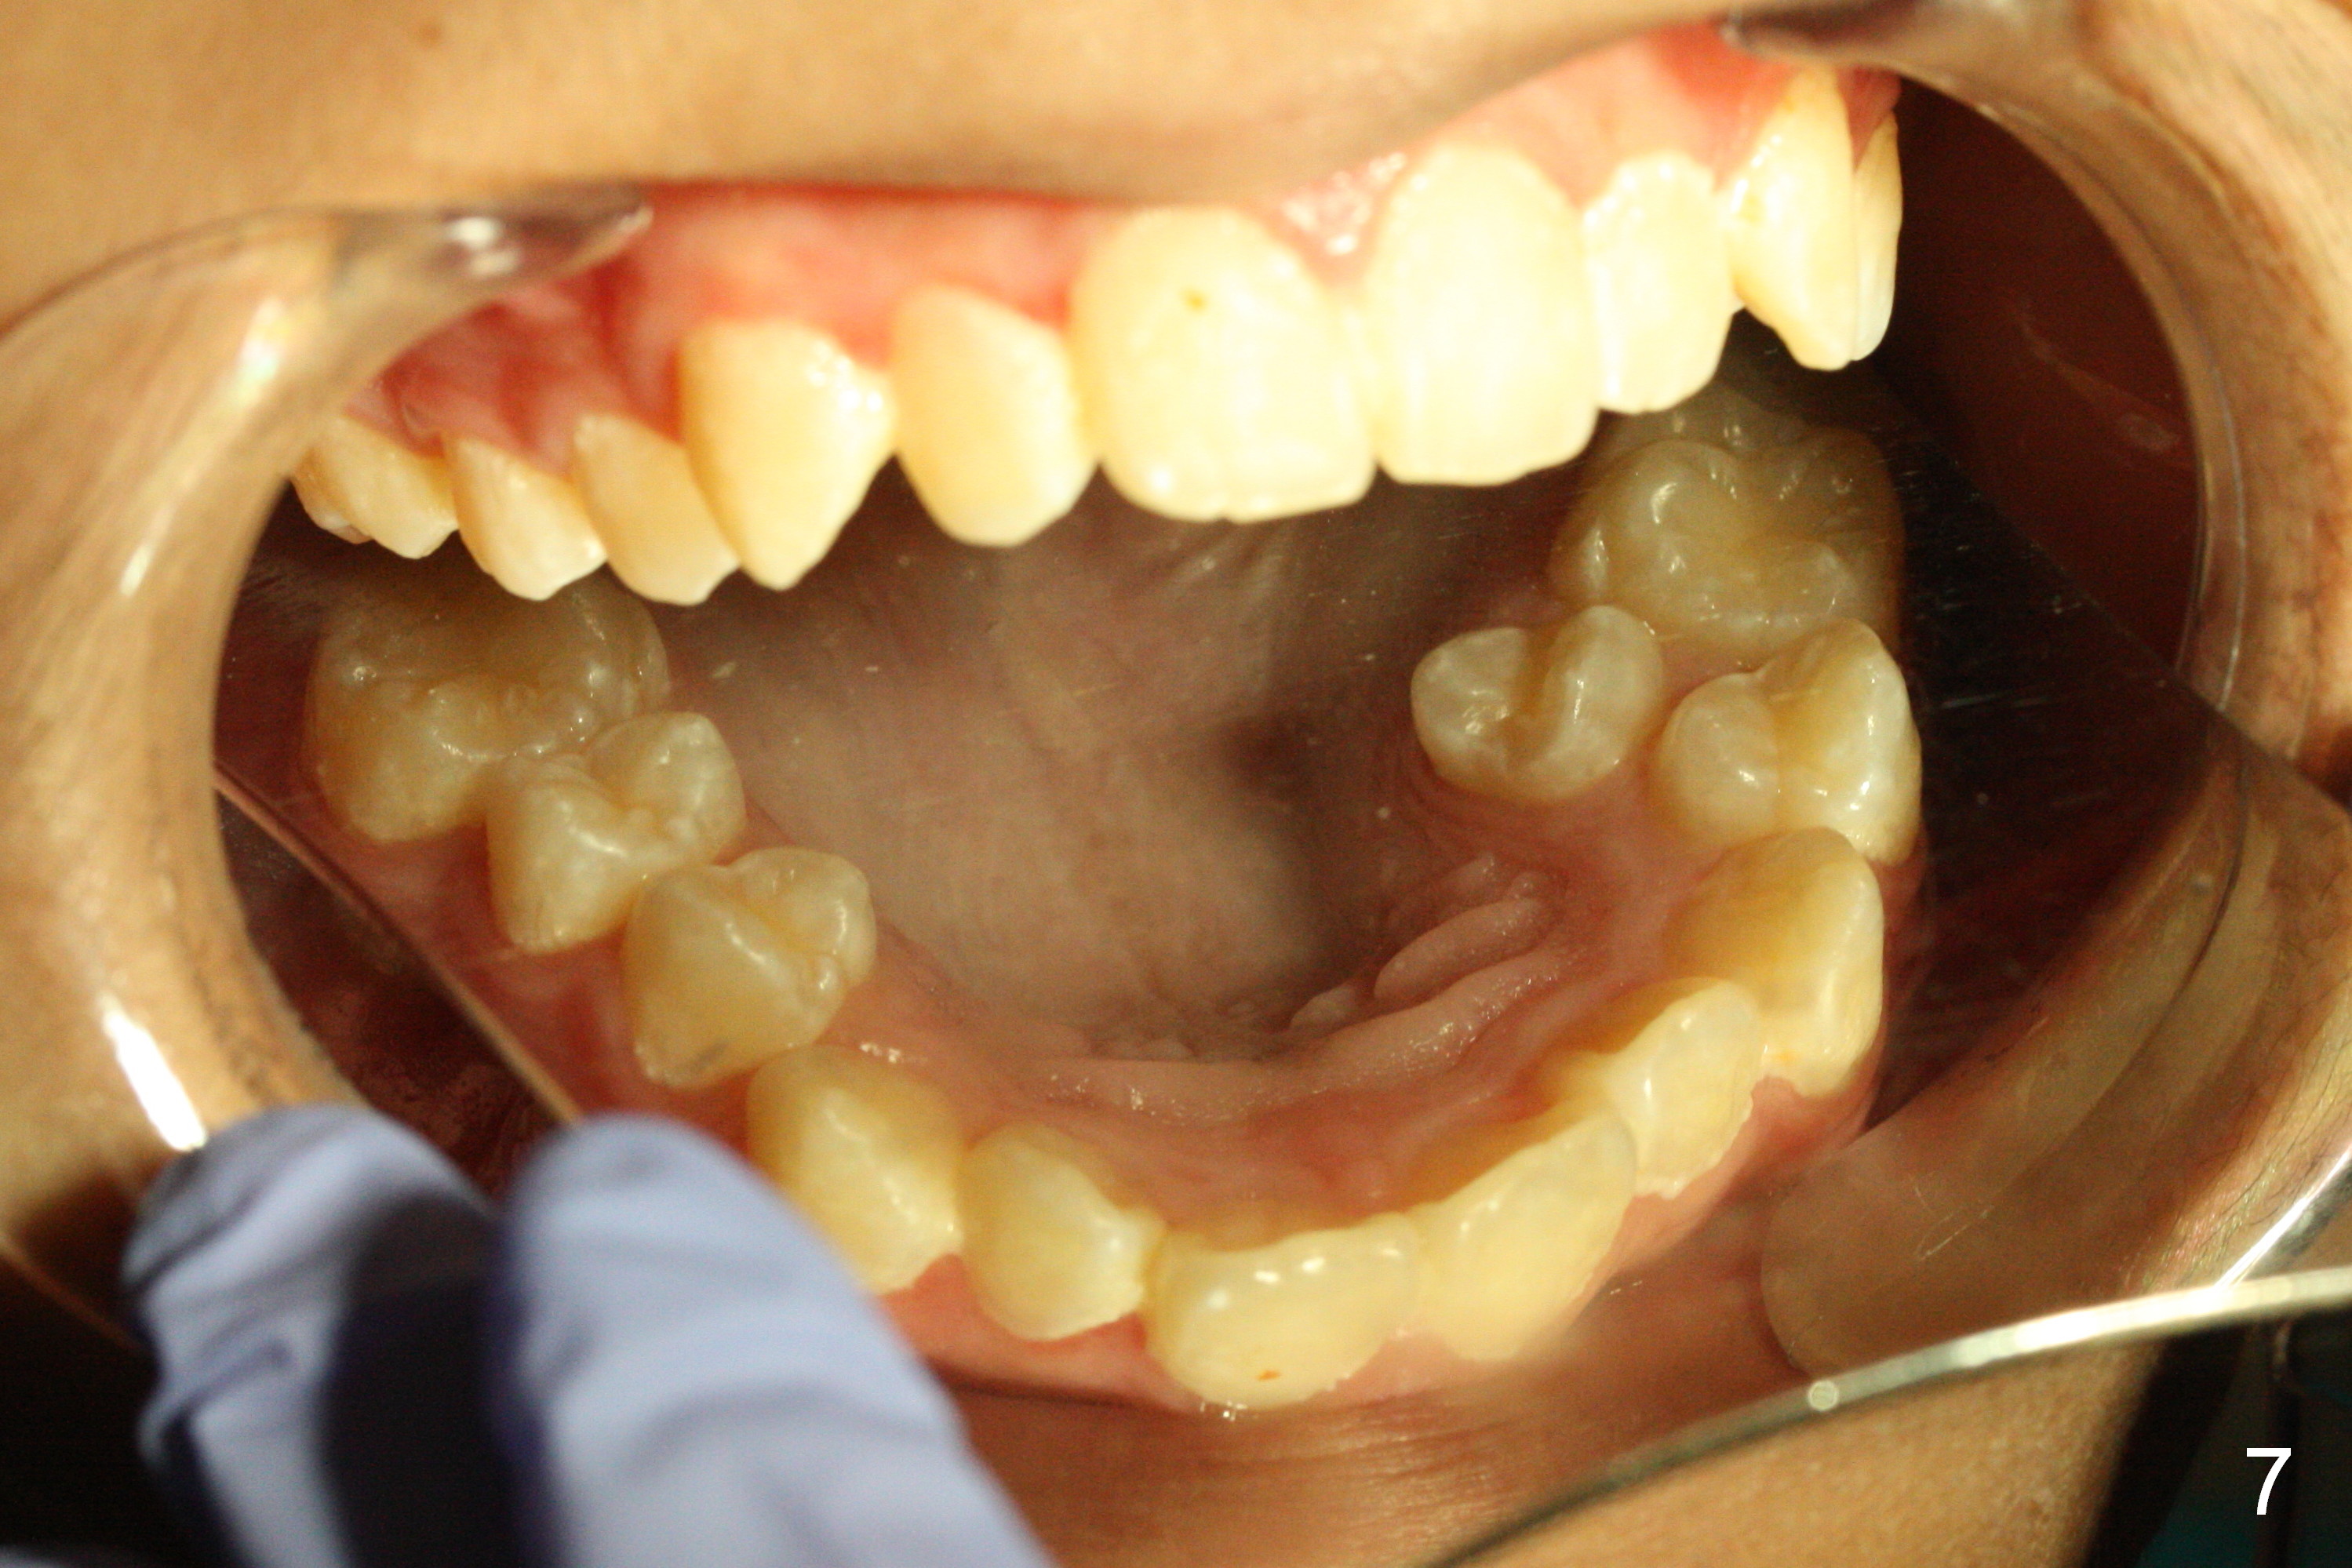

A 13-year-old man's malocclusion has two major components: upper midline deviation (Fig.2,5) and severe crowding (Fig.2,5-7).  His mother resists extraction, in spite of facial profile analysis (Fig.4,4').  A second obstacle to orthodontic treatment is his poor oral hygiene (Fig.5-7).  Before prophylaxis on Monday, can we decide together whether his oral hygiene has been improved drastically over the weekend?  If not, banding and bracketing will be canceled on Tuesday.